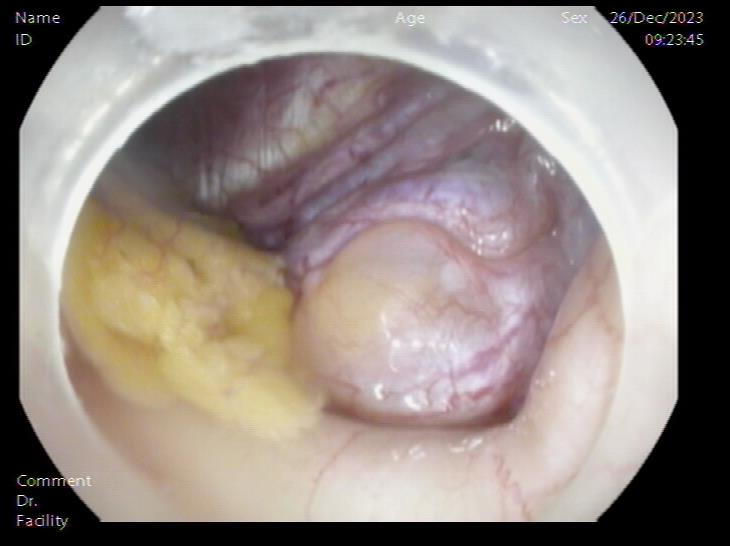

胃底SMT样隆起 内镜下切开刀行胃壁全层切开

腹腔内囊肿 腹腔内囊肿近景

囊肿切开引流,囊壁塌陷 内镜下胃壁全层缝合